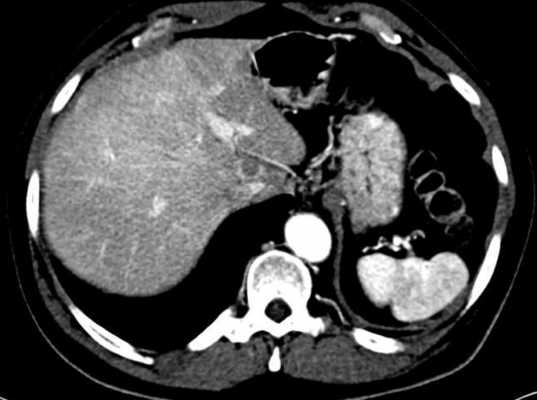

In the yearlong study, the UCLA team collected tumor samples from 107 people with soft-tissue sarcomas. Tumor fragments were then surgically implanted into the mice in the anatomic site corresponding to the original tumor location in the patient. The researchers assessed the ability of the models to successfully "establish," meaning that after implantation of the human tumor fragments in the mouse model, a new tumor grew. The tumor fragments could also be subsequently transferred and grown in additional mice for further testing, said Fritz Eilber, M.D., professor of surgery, Division of Surgical Oncology and chief of the Cancer Surgery Service at UCLA, and the senior author of the study.